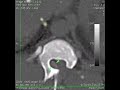

páteř / nádorové onemocnění

Nádorové onemocnění krčního úseku páteře u psa 10 let

Tumor v páteřním kanále po operaci údajné vyhřezlé ploténky.